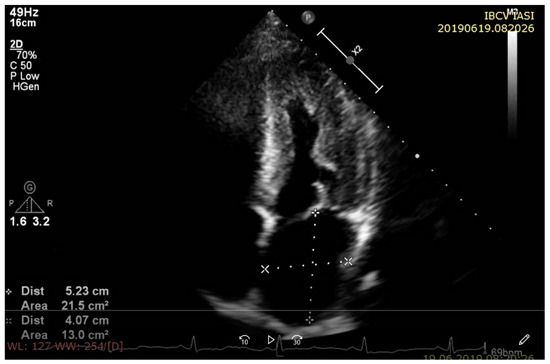

2.1. Left Ventricular Wall Thickness and Cavity Size

2.1.1. Left Ventricular Wall Thickness and Cavity Size in Amyloidosis

2.1.2. Left Ventricular Wall Thickness and Cavity Size in Sarcoidosis

2.1.3. Left Ventricular Wall Thickness and Cavity Size in Hemochromatosis